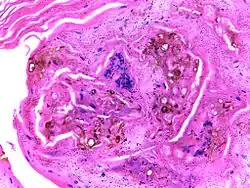

| Micrograph of chromoblastomycosis showing sclerotic bodies | |

The most informative test is to scrape the lesion and add potassium hydroxide (KOH), then examine it under a microscope. (KOH scrapings are commonly used to examine fungal infections.) The pathognomonic finding is observing medlar bodies (also called muriform bodies or sclerotic cells). Scrapings from the lesion can also be cultured to identify the organism involved. Blood tests and imaging studies are not commonly used. On histology, chromoblastomycosis manifests as pigmented yeasts resembling "copper pennies". Special stains, such as periodic acid Schiff and Gömöri methenamine silver, can be used to demonstrate the fungal organisms if needed.